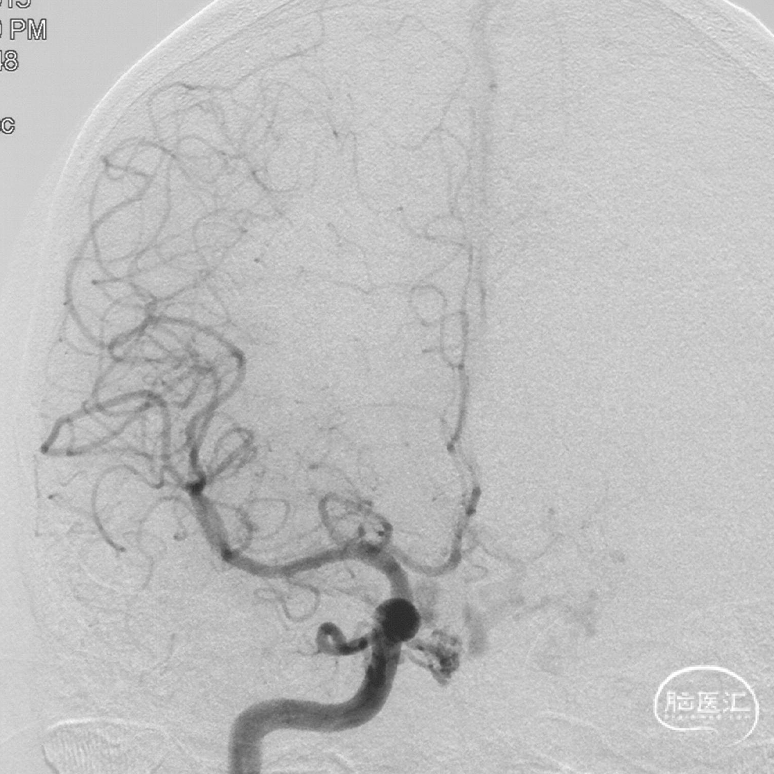

双侧颈内动脉正侧位造影见前颅窝底硬脑膜动静脉瘘,双侧筛前动脉、筛后动脉向瘘口供血,通过皮层静脉向上矢状窦引流。

双侧颈外动脉正侧位造影见镰前动脉向瘘口供血。

前颅窝底DAVF,由镰前动脉、双侧筛前、筛后动脉参与供血,通过皮层静脉向上矢状窦引流,引流静脉伴有瘤样扩张,Cognard IV型、Borden III型。由于脑膜中动脉-镰前动脉路径较为迂曲,超选困难,引流静脉迂曲扩张,预计到达瘘口起始端存在困难,决定经眼动脉-筛前动脉栓塞。

工作角度造影:黑色箭头为筛前动脉,白色箭头为筛后动脉,黄色箭头为镰前动脉,蓝色箭头为引流静脉起始部,红色箭头为视网膜中央动脉。拟通过眼动脉入路超选至筛前动脉进行栓塞。